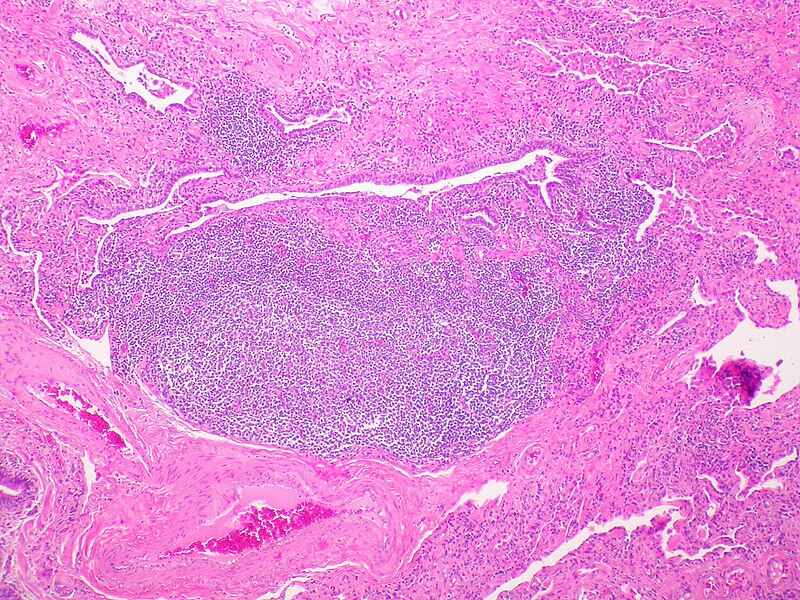

Arthritic changes – Arthritis is related to a condition of painful joints due to inflammation or swelling. A type of arthritis is rheumatoid arthritis, it is an autoimmune disease where the immune system attacks the joints, starting with the lining of joints. Rheumatoid arthritis is heavily related to lung problems, about 80% of arthritic patients have lung-related issues, making it the second leading cause of death with rheumatoid arthritis patients. Rheumatoid arthritis caused lung problems are most commonly extra-articular i.e., outside of the joints and involves pulmonary nodules; damage to the lung airways, pleural effusion and interstitial lung disease. In rheumatoid arthritis associated interstitial lung disease the auto-immune system gets over active and attacks the lungs and causes scarring. With time, the scarring build-up leads to difficulty breathing and reduced lung function.